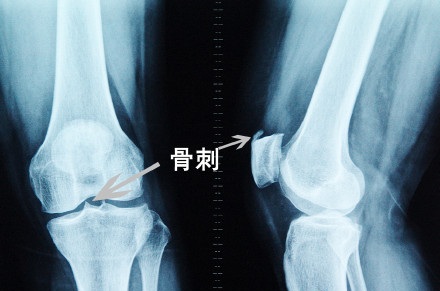

骨刺,是老百姓口中说的,医学上称之为“骨质增生”“骨赘”,这其实不是一个疾病,而是人体对于自身的一种保护机制,常常见于中老年人等骨质疏松有长时间负重下地的人,下面以膝关节骨质增生来举例,先来看看骨刺长啥样?